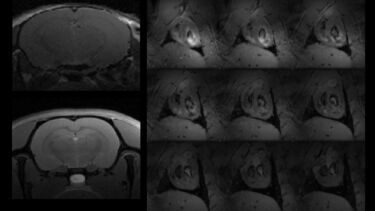

Zebrafish have become a ubiquitous animal model for studying a range of diseases and conditions. Typically, these studies are conducted in transparent juvenal fish where optical imaging techniques can be used. However, this is more difficult in adult zebrafish, restricting their use in longitudinal studies. Developed within the preclinical MRI facility, we have the capability to image live zebrafish. The animal can be scanned at high resolution (In plane, 50x50 μm, 200 μm slice thickness) with easy loading and full recovery to facilitate longitudinal studies.